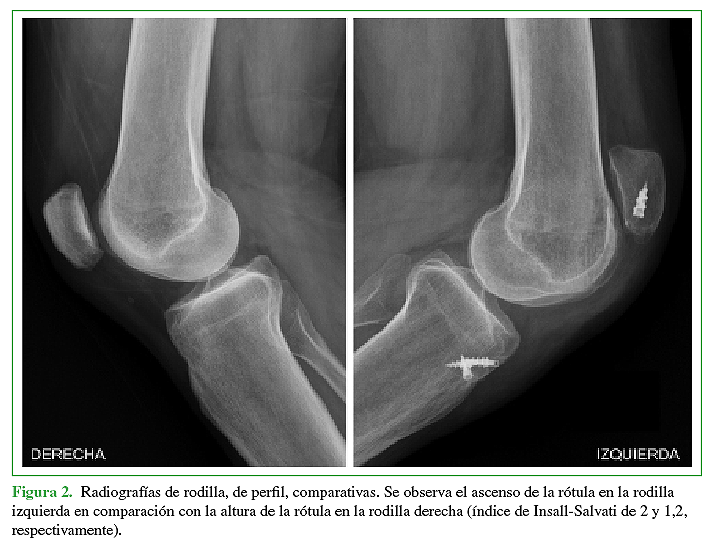

El objetivo de este trabajo es la presentación de un caso donde se realizó la reconstrucción quirúrgica del aparato extensor mediante la utilización de aloinjerto luego de haber presentado tres cirugías fallidas para la reparación del tendón rotuliano tras sufrir una lesión traumática del mismo. Se describe tanto la técnica quirúrgica como también el protocolo de rehabilitación.